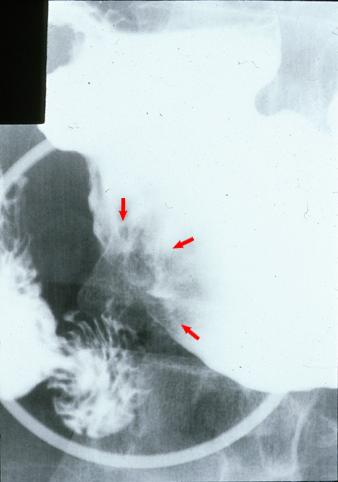

clasificación del pacienteTumor Epitelial Maligno/Adenocarcinoma

parte(separada por órganos)estómago(región)/ángulo

método de exámenRayos X

clasificación ectoscópica de tumoresTipo 0(tipo superficial)/Tipo IIa(IIa+IIc)

diámetro mayor del tumor20 - 24

grado de penetraciónsm